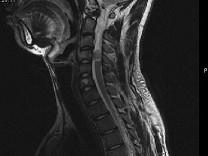

问题 男,24岁,颈部疼痛,并右上肢麻木,以手部明显,请根据所提供图像,选择最可能的诊断()

选项 A.(颈4~5)神经鞘瘤 B.(颈4~5)脊膜瘤 C.(颈4~5)海绵状血管瘤 D.(颈4~5)血管母细胞瘤 E.(颈4~5)胶质瘤

答案 A